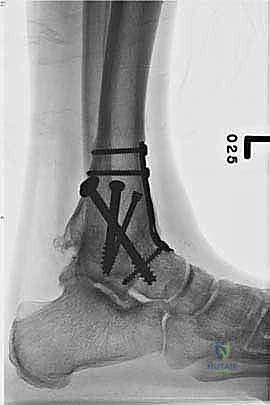

| طرق العلاج | أدوية مضادة للالتهابات (NSAIDs)، أحذية طبية مخصصة (Rocker-bottom shoes)، دعامات الكاحل (AFO)، حقن الكورتيزون أو البلازما (PRP)، العلاج الطبيعي. | جراحة إزالة الغضاريف التالفة ودمج العظام (Arthrodesis) باستخدام مسامير وألواح معدنية. |

- تثبيت ميكانيكي حيوي أقوى: يتيح المدخل الأمامي وضع شريحة معدنية (Anterior Plate) على الجانب الأمامي للمفصل. من الناحية الميكانيكية الحيوية (Biomechanics)، يعتبر الجانب الأمامي هو "جانب الشد" (Tension side) أثناء المشي. وضع الشريحة هنا يوفر تثبيتاً فائق القوة ويقلل من معدلات عدم الالتئام.

- التخطيط الجراحي الرقمي: باستخدام صور الأشعة المقطعية، يقوم الدكتور هطيف بتخطيط الجراحة على الكمبيوتر لاختيار حجم المسامير والشرائح المناسبة بدقة مليمترية.